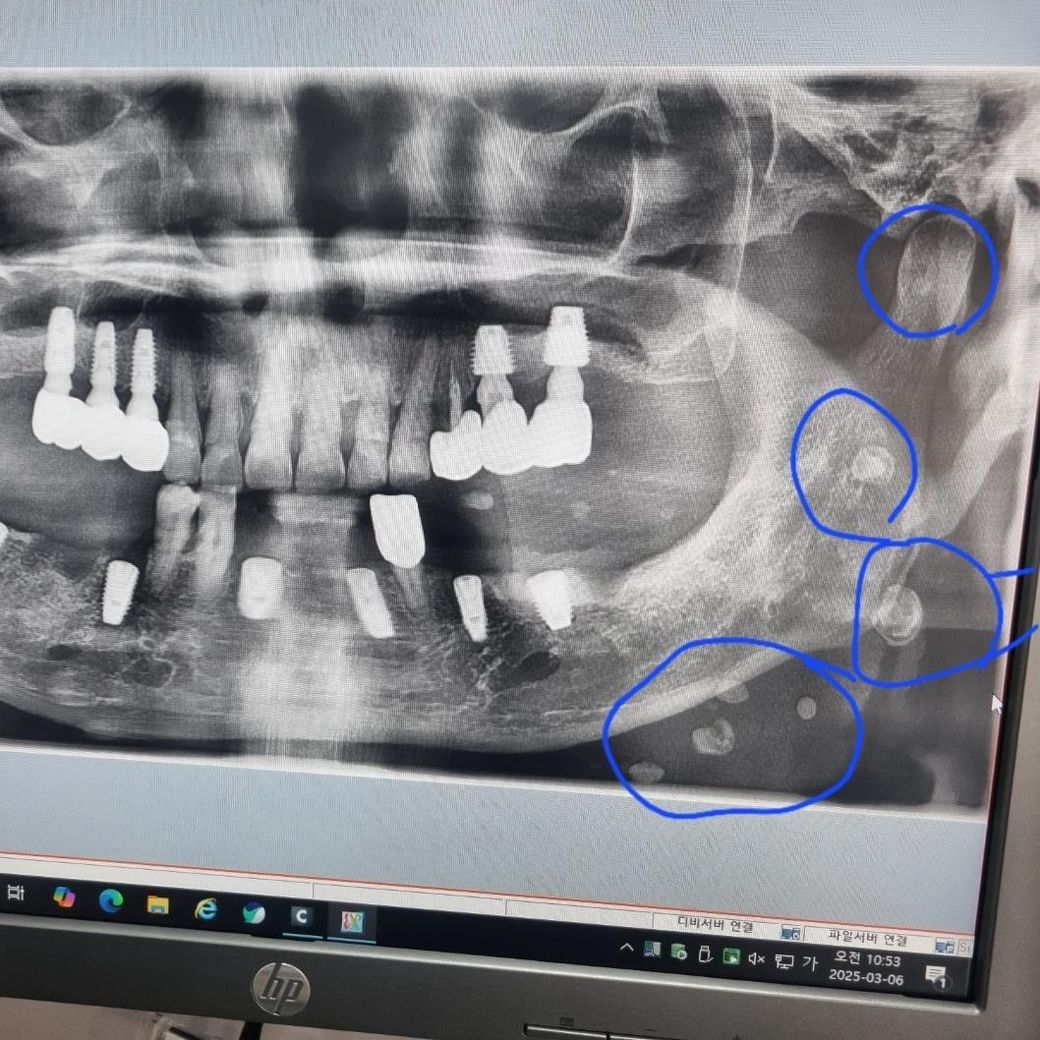

안녕하세요. 70대 아버지 치아 엑스레이 사진입니다. 현재 임플란트 식립중인데 엑스레이 상 턱부분에 하얀결절이 많이 보여서 걱정되서 문의드립니다.

하얀결절이 뭘까요? 큰병원에 가야 하는건가요?

현재 임플란트 주위 염증이 생성되었을 가능성 및 새로운 뼈가 형성되는 과정일 가능성이 있습니다. 보다 정확한 것은 진료를 통해 직접보아야 확인이 되기에 치과 진료를 받길 권합니다.

침샘에서 나타나는 결석이 아닐까 생각됩니다. 혹시 모르니 대학병원에 가셔서 검진을 다시 받아보시는게 좋을것같습니다.

파노라마 상 다수의 방사선불투과상 결절은 대표적으로 림프절 석회화, 편도결석(tonsillolitihs), 타석증(sialolitihs) 등입니다. 방사선 사진의 양상을 봐서는 림프절 석회화 가능성이 높습니다.